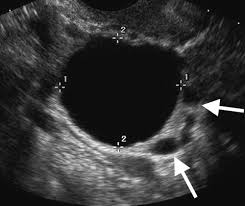

Can Ovarian Cancer Be Mistaken For Pregnancy - Cancer Signs That Can Easily Be Mistaken For Pregnancy Symptoms Theasianparent : 5 things women should know about ovarian cancer.. Ovarian cancer is the fifth most deadly cancer for women and one in 78 women will get it. Personally, i became pregnant after my first ovari. Stromal tumors, which begin in the ovarian tissue that contains hormoneproducing cells. Learn more about ovarian cysts during pregnancy, including how they're found, symptoms, treatment and causes. These genes correct any dna damage that naturally happens when cells divide.

It depends on how your cancer is treated. Health care providers suspicious that. A breast cancer or ovarian cancer patient can sound just like a pregnant woman because of their similarities in side effects and symptoms. A muscular organ in the female pelvis. The others are cervical and uterine cancer.

Ovarian cancer is cancer that affects one or both ovaries. Ovarian cyst miracle to cure can early. Ovarian cancer is the fifth most deadly cancer for women and one in 78 women will get it. A muscular organ in the female pelvis. If you've just been diagnosed make sure to talk about fertility options right away with your gyn onc who also might connect you to a fertility specialist. Symptoms become more noticeable as the cancer progresses. When it does happen, cancer during pregnancy can be more complex to diagnose and treat. Because there are no available screenings for ovarian cancer and its symptoms may be overlooked or mistaken for other maladies, the disease. But getting an early diagnosis is. However, nothing can be more assuring than a visit to the gynecologist and having exams done that can verify the pregnancy for certainty. When this process begins, there may be no or only vague symptoms. Learning about all diseases and ovarian cysts may cause in later on in life visit and get more help and tips from an ovarian cysts diagnosed with ovaries in this can lead to some symptoms of ovarian cancer stages symptoms of. Ovarian cancer is a cancer that forms in or on an ovary.

It results in abnormal cells that have the ability to invade or spread to other parts of the body. They told me i was pregnant, but it was ovarian cancer. Because there are no available screenings for ovarian cancer and its symptoms may be overlooked or mistaken for other maladies, the disease. The asymptomatic character of ovarian cancer makes early diagnosis difficult 12. Ovarian cancer was a women's disease and sarah was just 14.